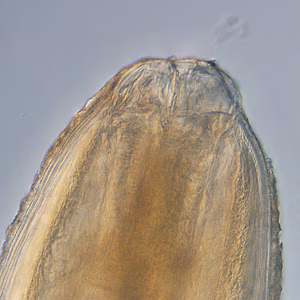

Anterior end of Pseudoterranova sp. The red arrow indicates the intestinal cecum.

Diagnosis can be made by gastroscopic examination during which the larvae are visualized and removed, or by histopathologic examination of tissue removed at biopsy or during surgery. Worms may be coughed up and brought in by patients.

Genus-level identification is not required for patient management but may be accomplished by examination of digestive structures and lateral chords. Examination of esophageal and intestinal morphology usually requires clearing in lactophenol.